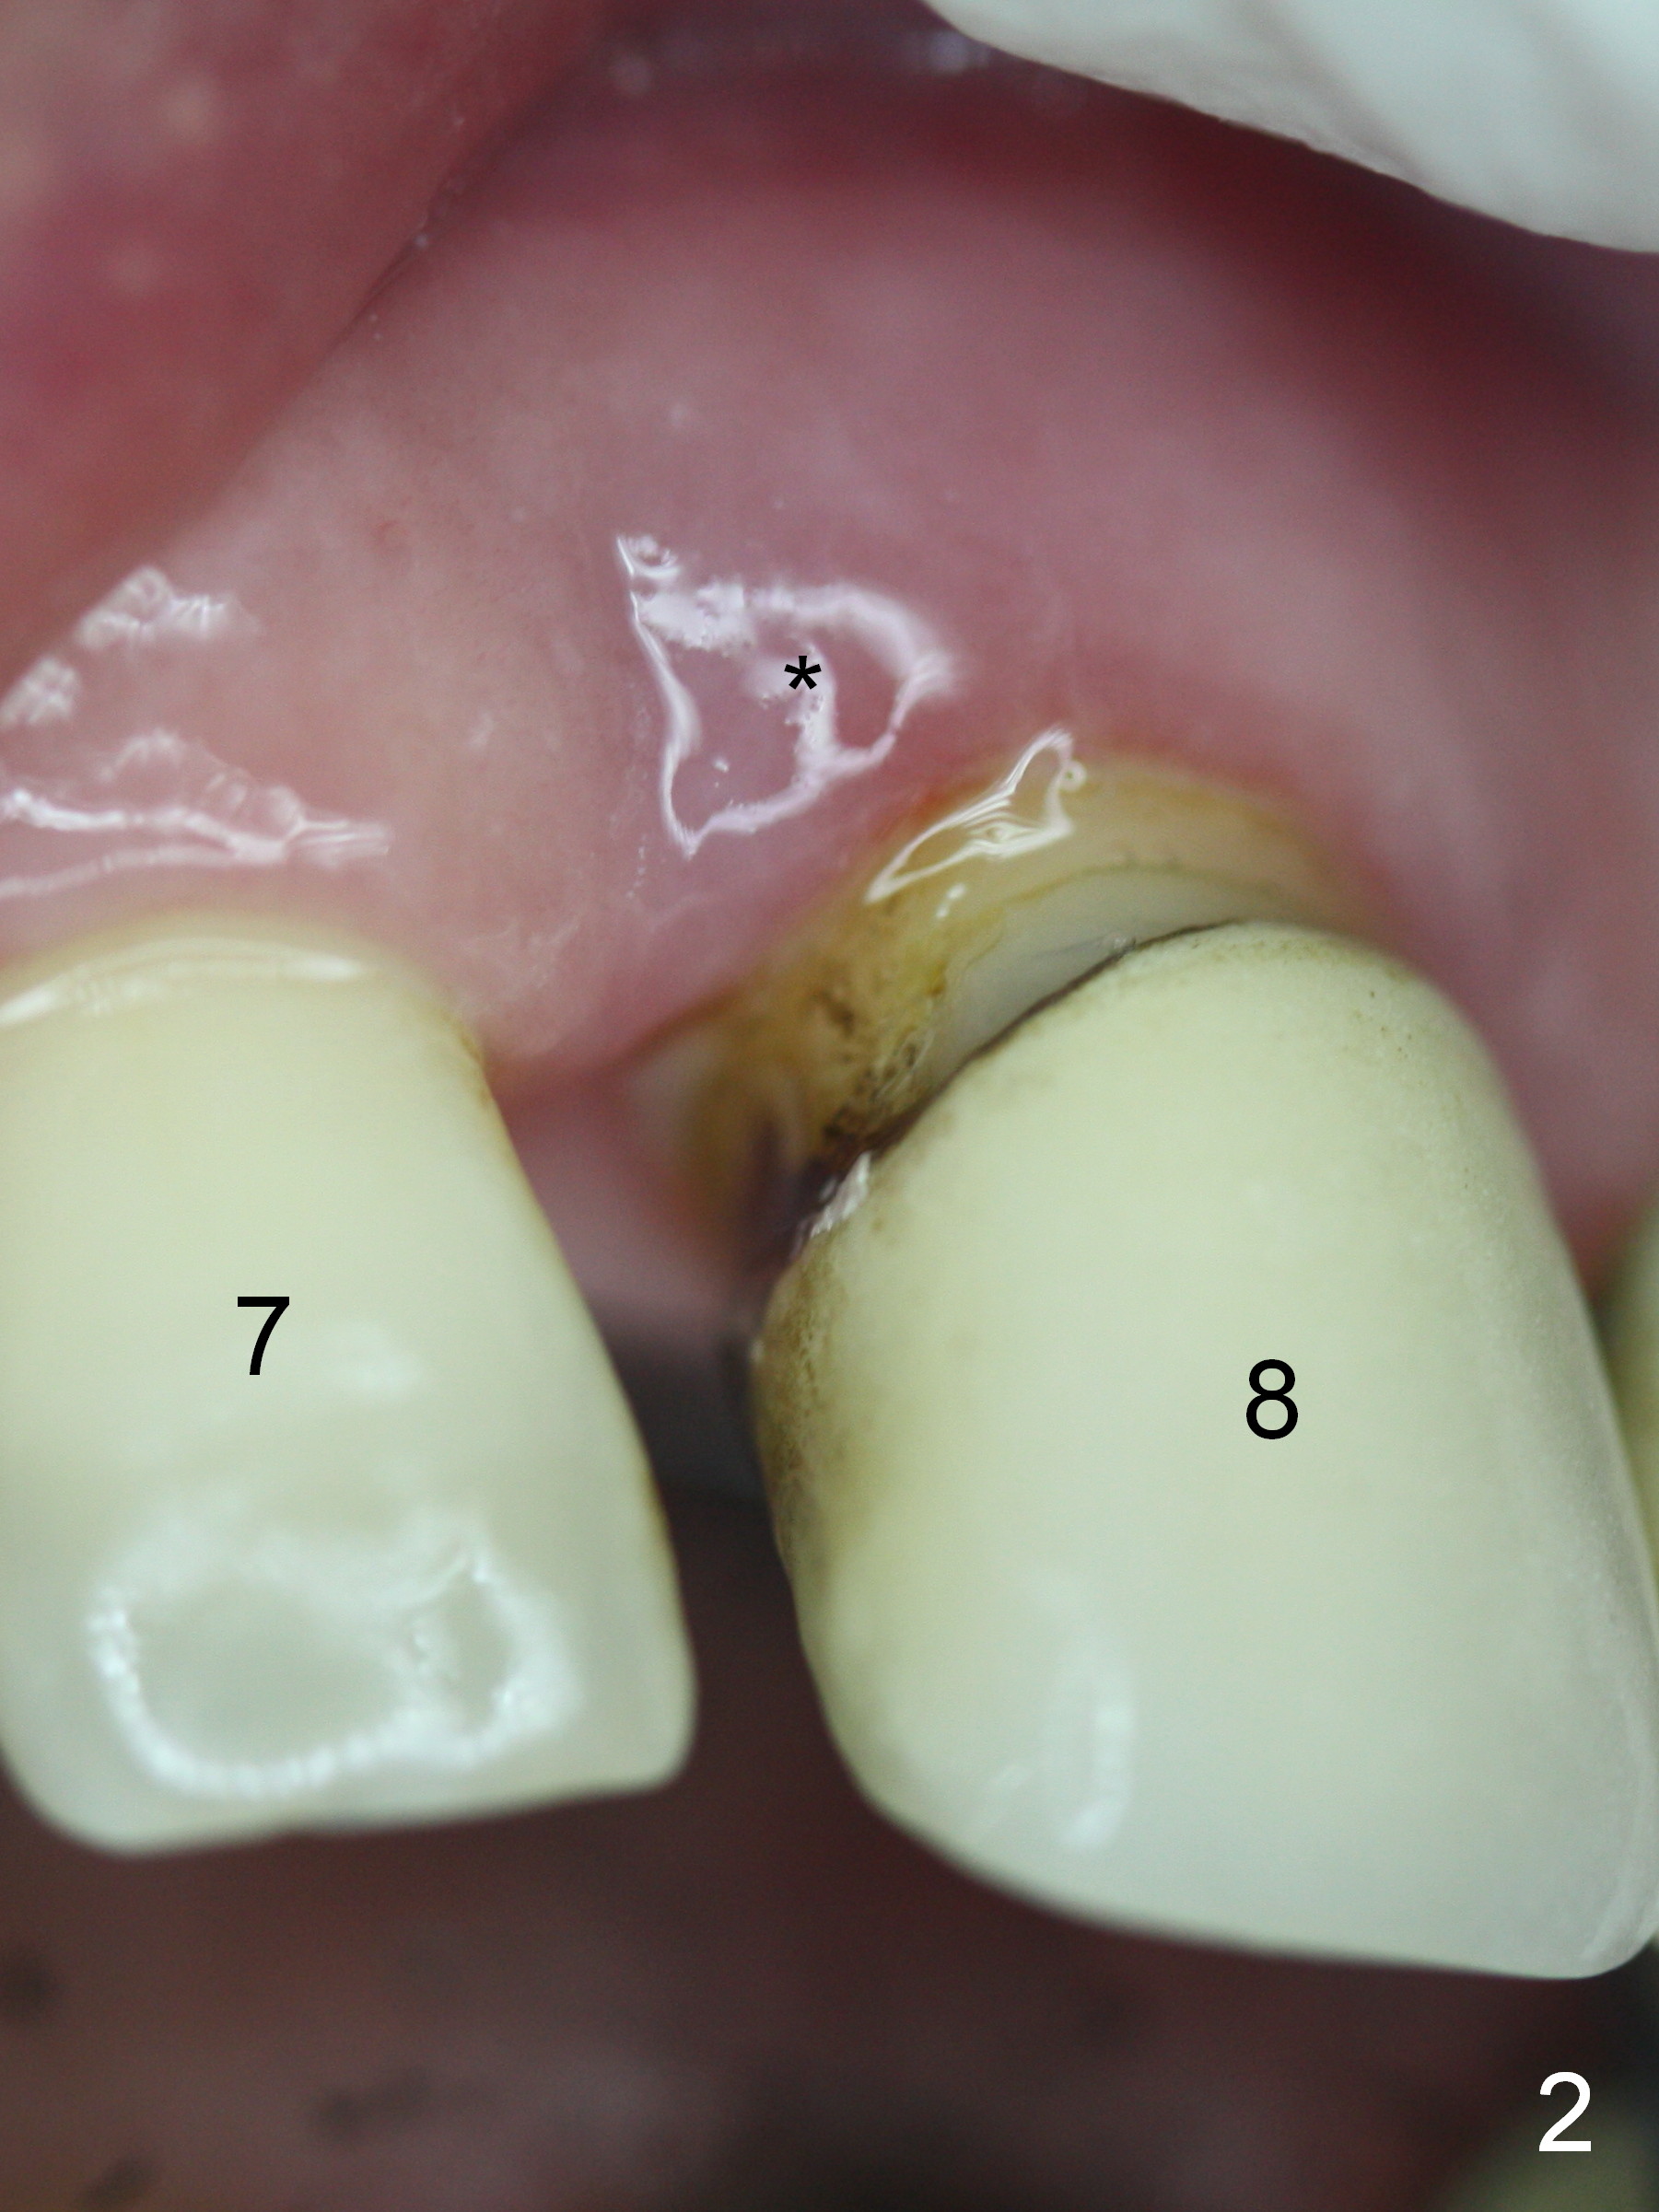

The 74-year-old patient is excited about having 3 implants placed without discomfort (1,2). He wants to take care of a loose FPD spanning from #8 to 9 (Fig.1). It appears that #8 is non-salvageable (Fig.2 * with deep pockets). There is severe bone loss around the affected tooth (Fig.3; Osteotape is expected for buccal and lingual defects). In addition, the Incisive Canal is abnormally large (arrowheads). The coronal end of a 4.5x20 mm implant and a 3.5x5 mm abutment will be slightly deviated mesially (Fig.4), since the 3-unit FPD will be converted to 2 single unit crowns. Surgical guide is ready. The 1st step is to section between #8 and the pontic (Fig.5; green outline: implant; red: abutment). If primary stability is low, the immediate provisional (Fig.8 white area) will be bonded the tooth #7 and the pontic as a supplementary measure (blue areas). Once the implant is osteointegrated, the distal portion of the pontic (Fig.7 *) will be removed. Acrylic is added to the mesial portion of the provisional (Fig.8 *) so that the papilla (P in Fig.7) will be pushed mesially and incisally (Fig.8 arrowheads). The step will be repeated a few weeks later (Fig.9). It could be done bilaterally at the same time by removing #9 crown and converting to the provisional. Finally the pontic will be removed. Two relatively wide crowns will be fabricated if the patient is satisfied with the provisional.